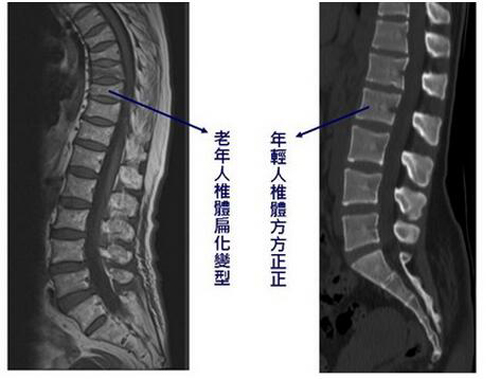

一般来说,上半身的高度是由脊椎的长度决定,分别由颈椎、胸椎及腰椎共24节组成,脊椎体和椎间盘会因为老化、贺尔蒙减少、甲状腺疾病、长期使用类固醇(如:气喘)、维他命D不足、体重太轻(如:过度节食、恶病体质)等因素,导致椎体密度慢慢空洞化,最后被压扁,形成民众熟知的骨质疏松。 只要每节椎体少0.1公分,身高至少矮2.4公分,若椎体前后两面扁平化的程度不一样,就会出现驼背现象。

想确认自己脊椎体是否有扁平化状况,可将背靠墙,脚跟和臀部紧贴墙壁,两眼平视前方,再测量后脑勺与墙壁间的距离,若大于5公分表示已出现扁平化现象;此外骨质密度检测更是较有科学根据的检查,运用患者测出之数据和20岁年轻人的平均数据相比较,若超过一定范围即表示有骨质疏松, 脊椎体有空洞及扁平化,身高当然就会变矮。